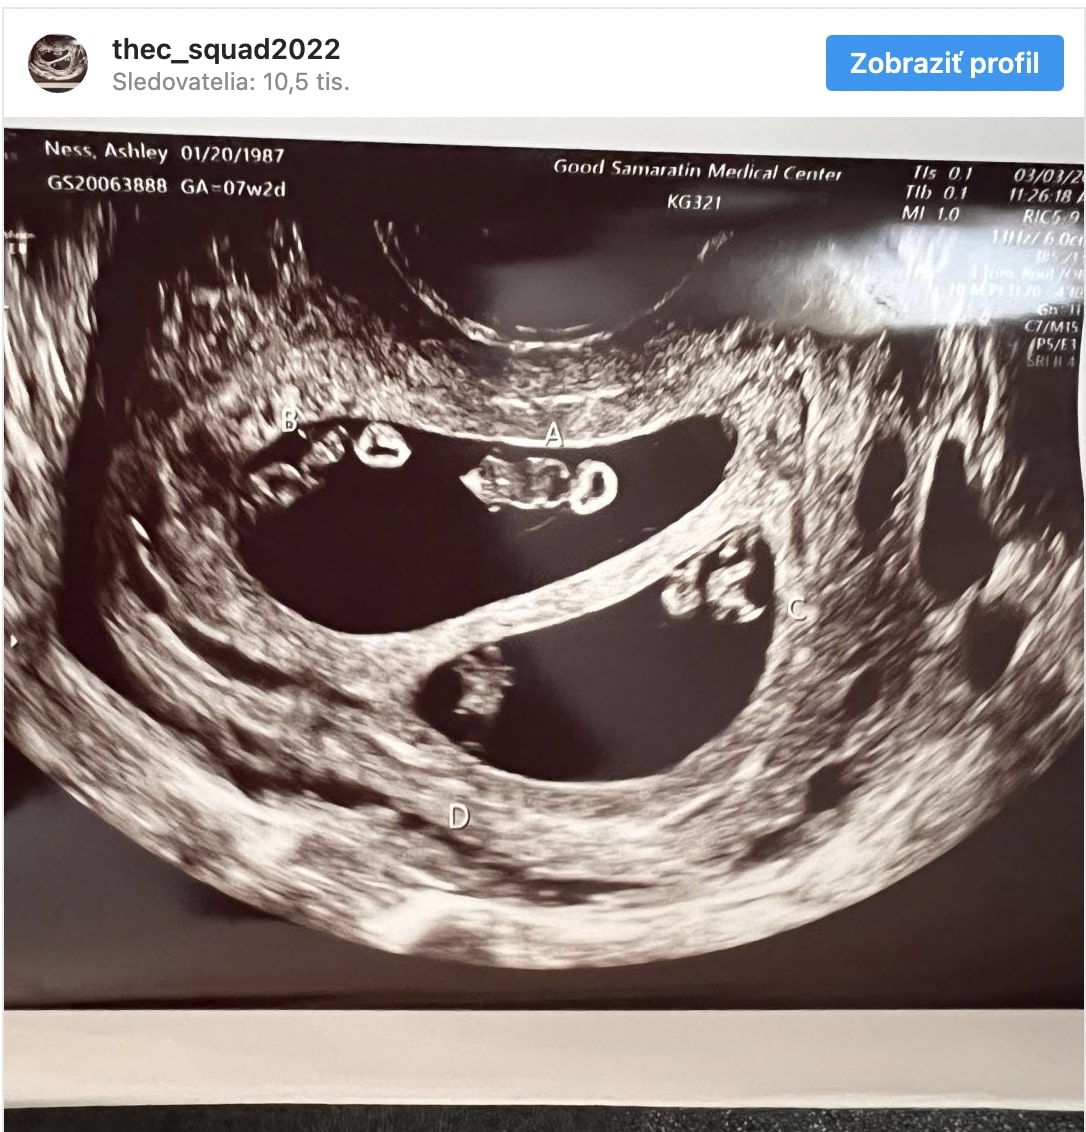

Lekár, ktorý poskytol rozhovor magazínu People, uviedol, že pravdepodobnosť tehotenstva, aké má Ashley, je 1 ku 10 miliónom. Počas bežného ultrazvuku sa totiž ukázalo, že žena nenosí pod srdcom jedno či dve deti, ale štvorčatá – dva páry jednovaječných dvojičiek.